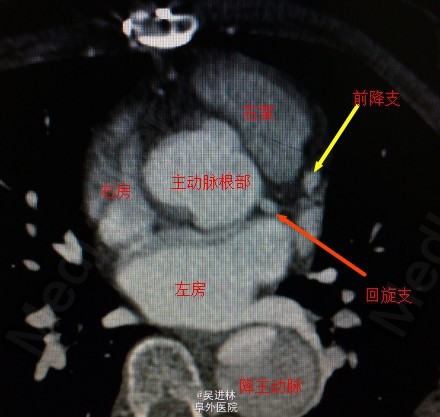

讨论:这一例病人做完手术的时候心电图显示ST段抬高,术后超声心动示左房后壁几乎无运动,于是仔细查看胸部CT,原来这个病人有三个冠状窦开口!也就是回旋支和前降支分别开口于主动脉根部,一共有3个冠状动脉开口!但是bentall手术只吻合了两个冠状窦口,造成病人心肌(左心室后壁——回旋支供血区)缺血。冠状动脉开口变异非常罕见,这真是百密必有一疏,希望大家引以为戒。二进宫时,患者右心跳动良好,左心基本无跳动,于是安置左心引流管,分流一部分血液出来,减轻左心室前负荷。